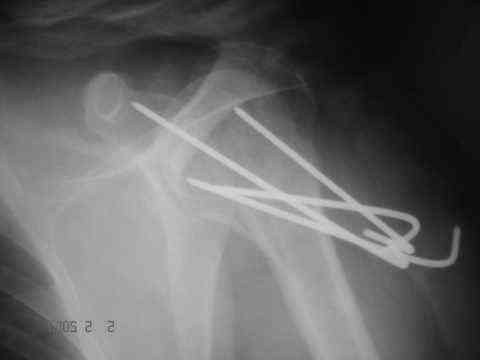

Dear all, A heavy built 30-year-old male patient sustained fracture dislocation of left shoulder about 8 months back.

For this ORIF with K-wires was done elsewhere. K-wires were removed at 6 weeks and patient advised physiotherapy. He has been doing physio dedicatedly since then.

Looking at his previous x-rays, I was thinking of refixing the greater tuberosity, however got anaxillary view done today which was never done during this period and this shows non-union.

It looks like the initial injury was a head splitting fracture. Presently the patient has a non-union at the level of the anatomical neck with displaced tuberosities. I would tackle the non-union, and would try to replace the tuberosities, a difficult procedure. I would use the proximal humerus locking plate from the AO.